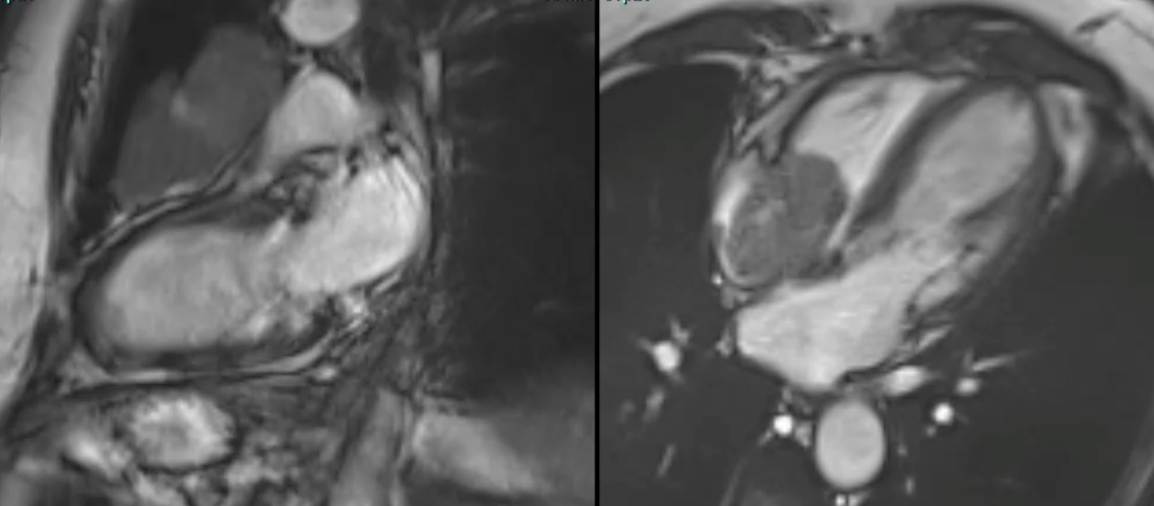

Tumors

Cardiac Mass